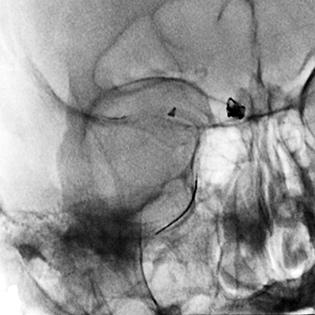

Recently, the limits of large bore aspiration have been pushed even further, as early experiences have been published reporting the safe use of 0.088” lumen aspiration catheters to perform MCA thrombectomies (Figure 4) (65). Other 0.088” aspiration catheters are currently undergoing benchtop testing (66), and more exotic designs (such as the R4Q, MIVI Neuroscience, Inc., Eden Prairie, MN) have been offered to increase function lumen size without increasing the outer catheter diameter (67). While it is thought that such large lumen sizes may improve recanalization rates by offering higher suction force as well as a degree of flow restriction proximal to the clot, evidence for the benefits of large bore aspiration is not unequivocal, and controlled trials will be necessary (68).

Fig 4

Figure 4. An 0.088” catheter (ZOOM 88, Imperative Care, Fremont, CA) located in the M1 MCA during thrombectomy.